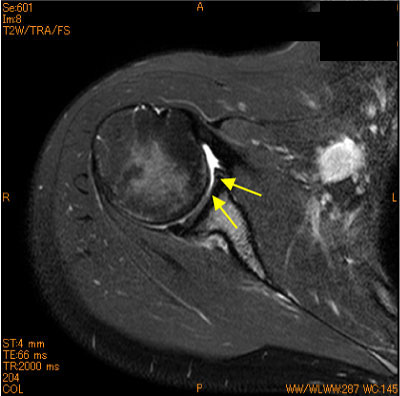

10代女性、ソフトボール歴11年、投球時痛、 関節窩前下方の軟骨欠損を認めている。

腱板損傷、関節唇損傷が疑われていたがintactであった。

先入観にとらわれない読影が重要である。